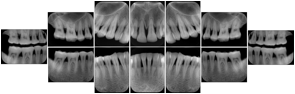

Intra-oral radiography typically involves acquisition of multiple images of various parts of the dentition. Many digital radiographic systems offer customized templates that are used for displaying the images in a study on the screen. These templates may also be referred to as mounts or view sets. The Structured Display Object represents a standard method of encoding and exchanging the layout and intended display of Structured Displays. A structured display object created in this manner could be stored with a study and exchanged with images to allow for complete reproduction of the original exam.

In most standard cases, images are oriented in structured layouts. These structured displays are useful to be shared between providers for reference purposes.

Table OO.1.1-1 shows structured display standard templates, where Viewset ID is based on the Japanese Society for Oral and Maxillofacial Radiology (JSOMR) classification provided by JIRA (Japan Medical Imaging and Radiological Systems Industries Association, www.jira-net.or.jp). Expected or typical teeth to be imaged location, region and designation codes are based on ISO 3950-2010, Dentistry - Designation system for teeth and areas of the oral cavity. For all the hanging protocols listed in OO.1.1-1, the value to use for Hanging Protocol Creator (0072,0008) is "JSOMR" and the value to use for Hanging Protocol Name (0072,0002) does not include "JSOMR" (e.g., "DL-S001A", not "JSOMR DL-S001A").